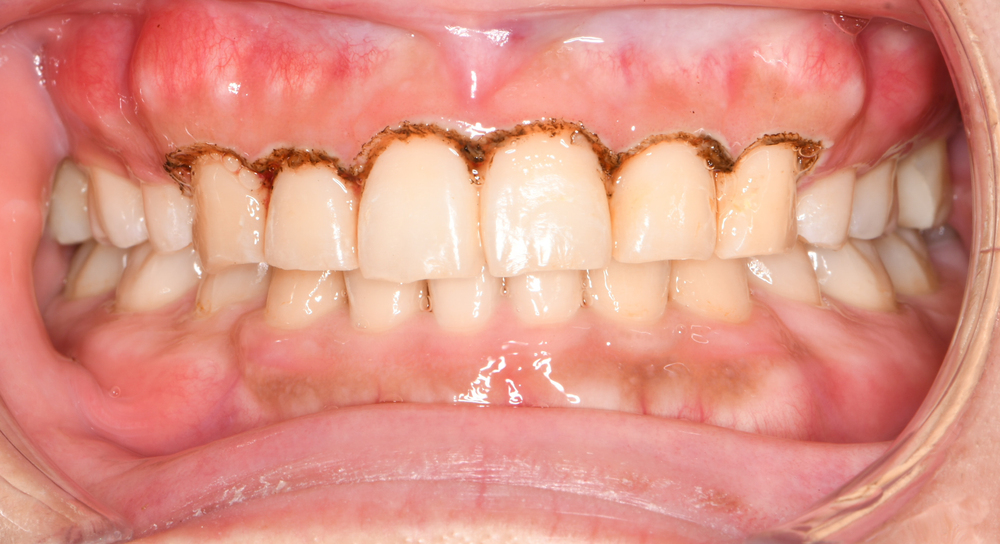

口腔内写真(正面)です。

上顎の正中線に対して下顎の正中線が右側へがわずかにズレています。

口腔内の写真です。まずは正面です。

上下顎の正中線も顔面正中を基準にぴったりと合っています。

また個々の歯の位置異常が適切に整えられていることがお分かりいただけると思います。